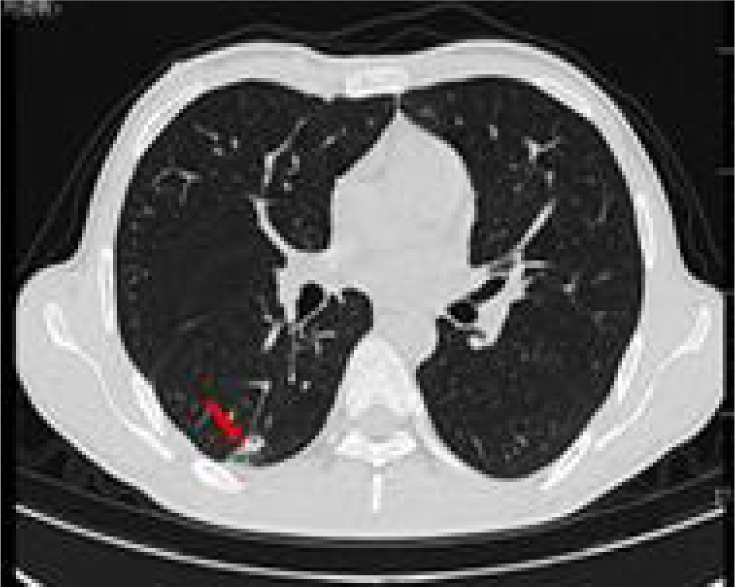

Full abdominal CT and lung CT revealed a high-risk pulmonary nodule in the right lower lobe (Figure 4), pancreatic enlargement with multiple cystic lesions, and multiple ill-defined low-density lesions in both kidneys (Figure 5).

Figure 4: Lung CAT (CT) shows a ground glass nodule (12×9 mm) in the posterior basal segment of the right lower lobe (IM51), with signs of pleural depression (red arrow).

Figure 5: Full abdominal CAT (CT) scan shows pancreatic enlargement with (A) multiple cystic foci and scattered calcification in the pancreas (red arrow), and (B) multiple low-density nodules in the kidney (red arrow).